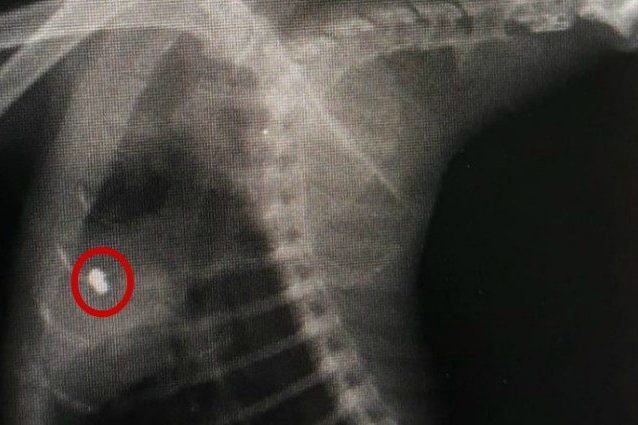

L'associazione Earth ha denunciato su Facebook un gatto ferito con una pistola a piombini nel quartiere di Torre Angela a Roma. Portato nella clinica veterinaria Borghesiana, il veterinario ha spiegato che non si tratta del primo caso, ma che sarebbero già quattro in un mese i mici curati per lo stesso motivo.